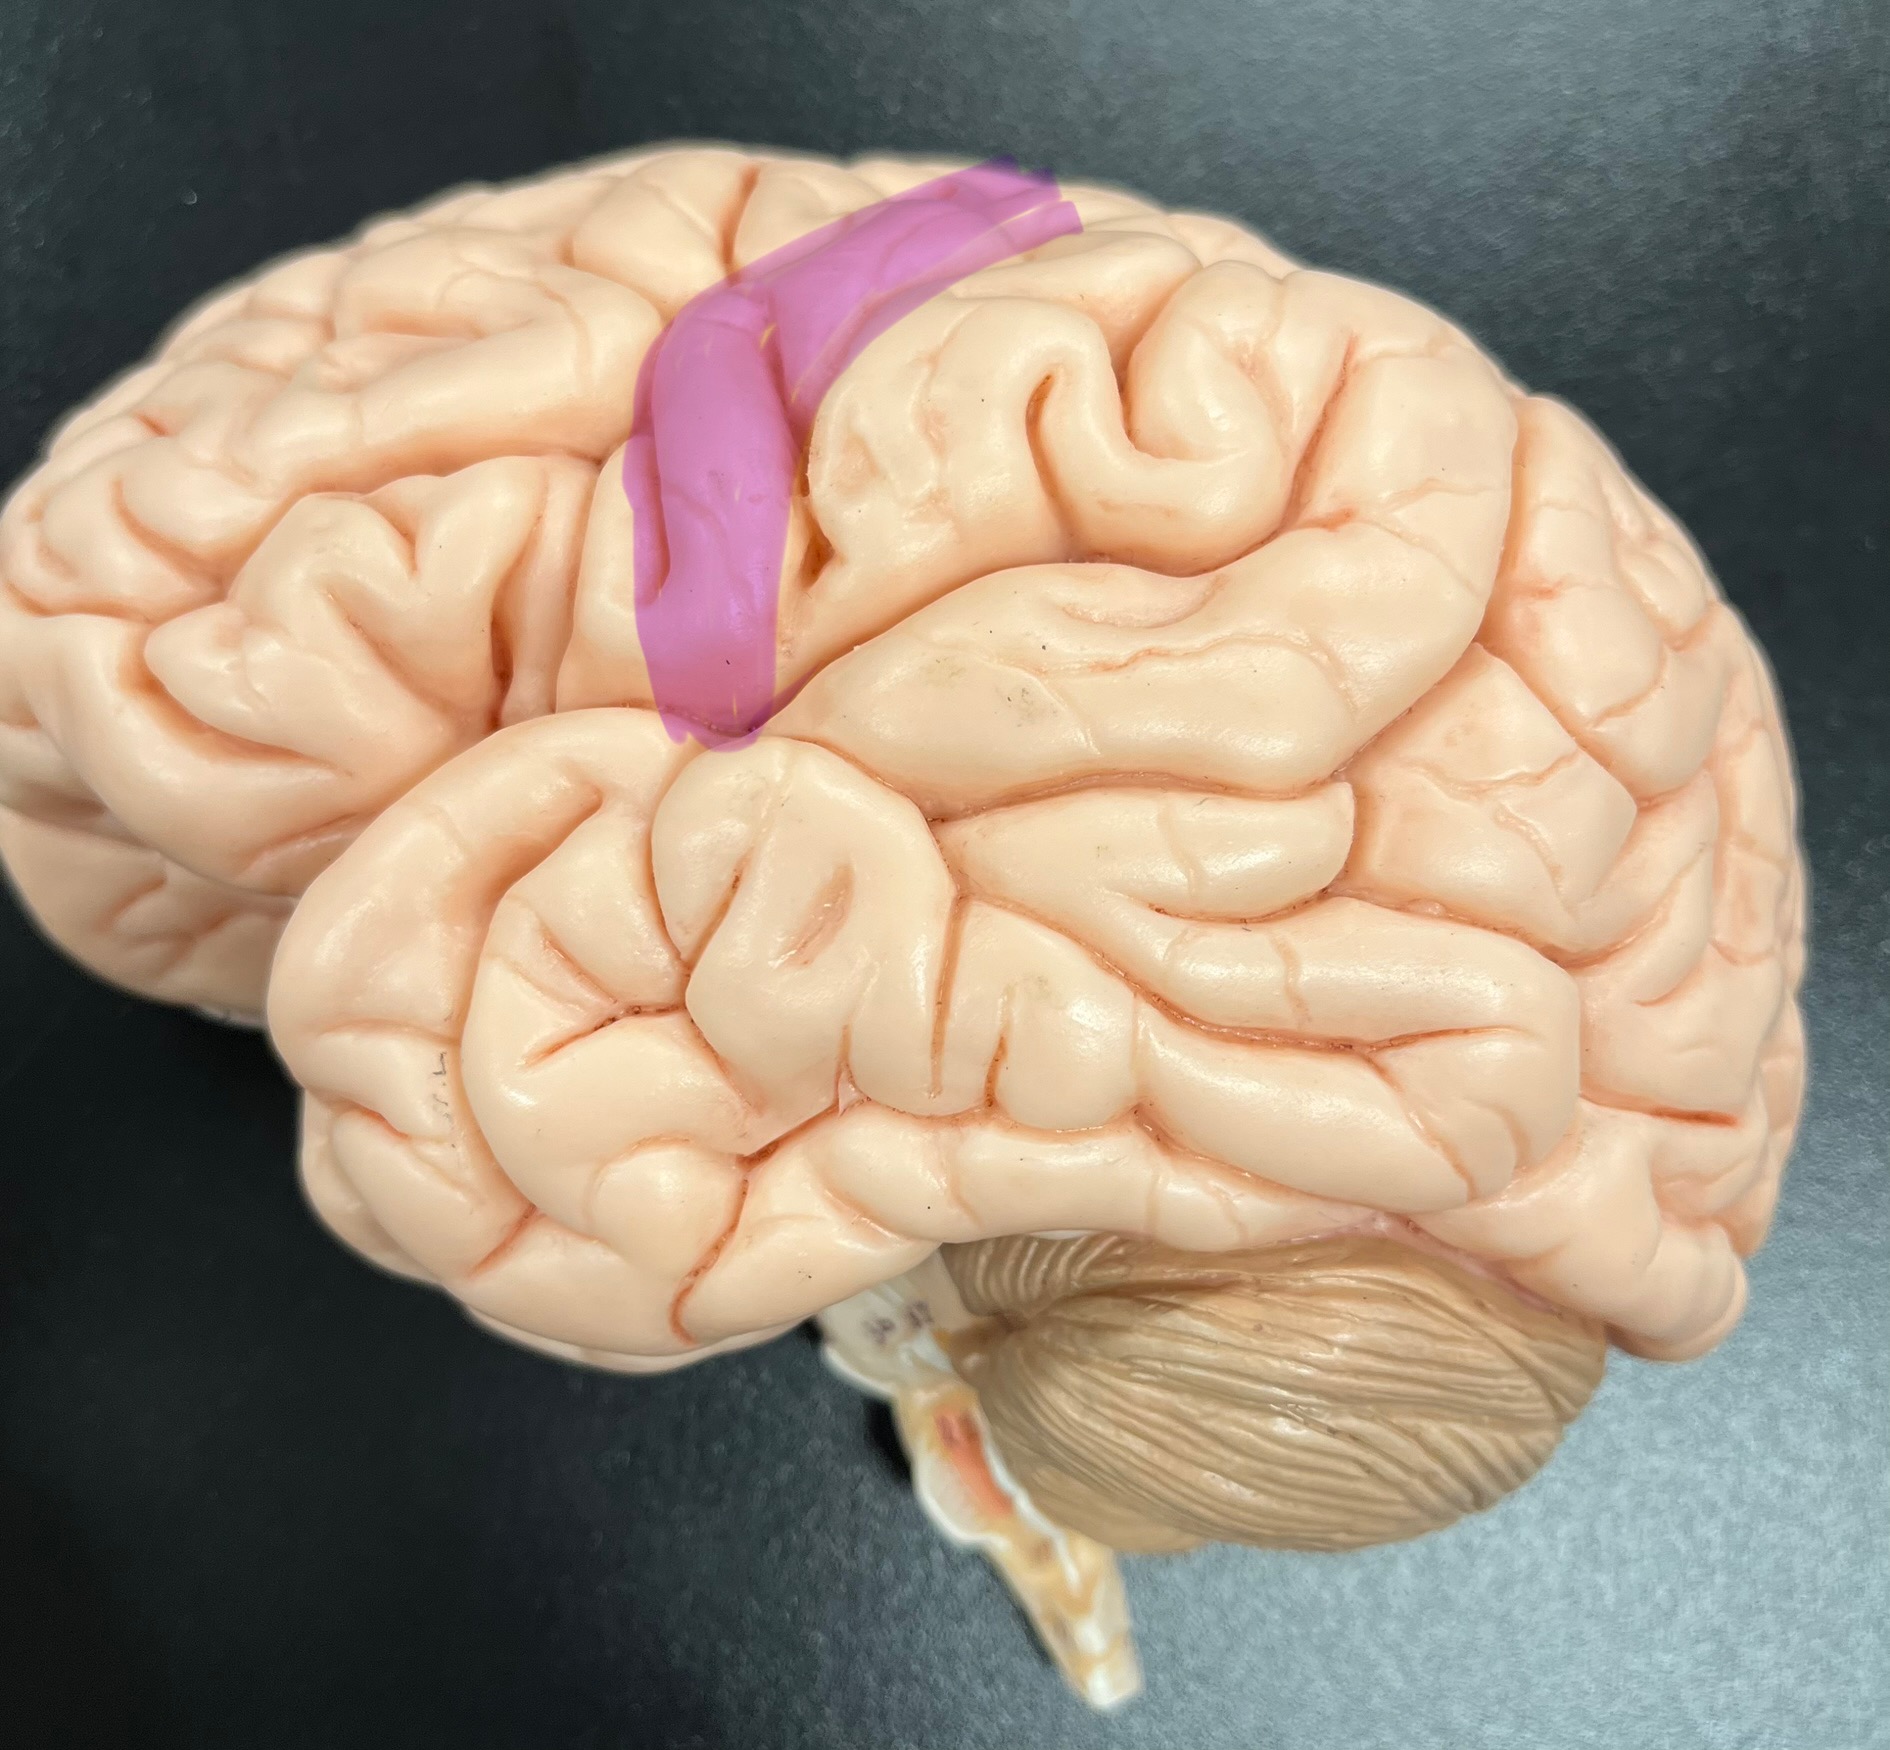

Divides parietal from frontal lobe

central sulcus

precentral gyrus

postcentral gyrus